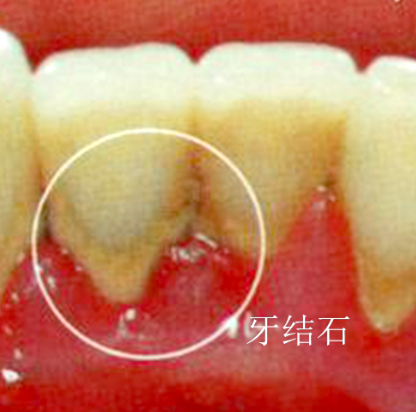

牙結石,也稱為牙石,是由牙齒表面的食物殘渣、細菌和唾液中的礦物質逐漸硬化形成的沉積物。它不僅影響美觀,還可能引發一系列口腔健康問題,如牙齦炎、牙周病等。為了保持口腔衛生,防止牙結石的形成,珠海鼎植口腔醫院建議遵循以下預防指南至關重要。